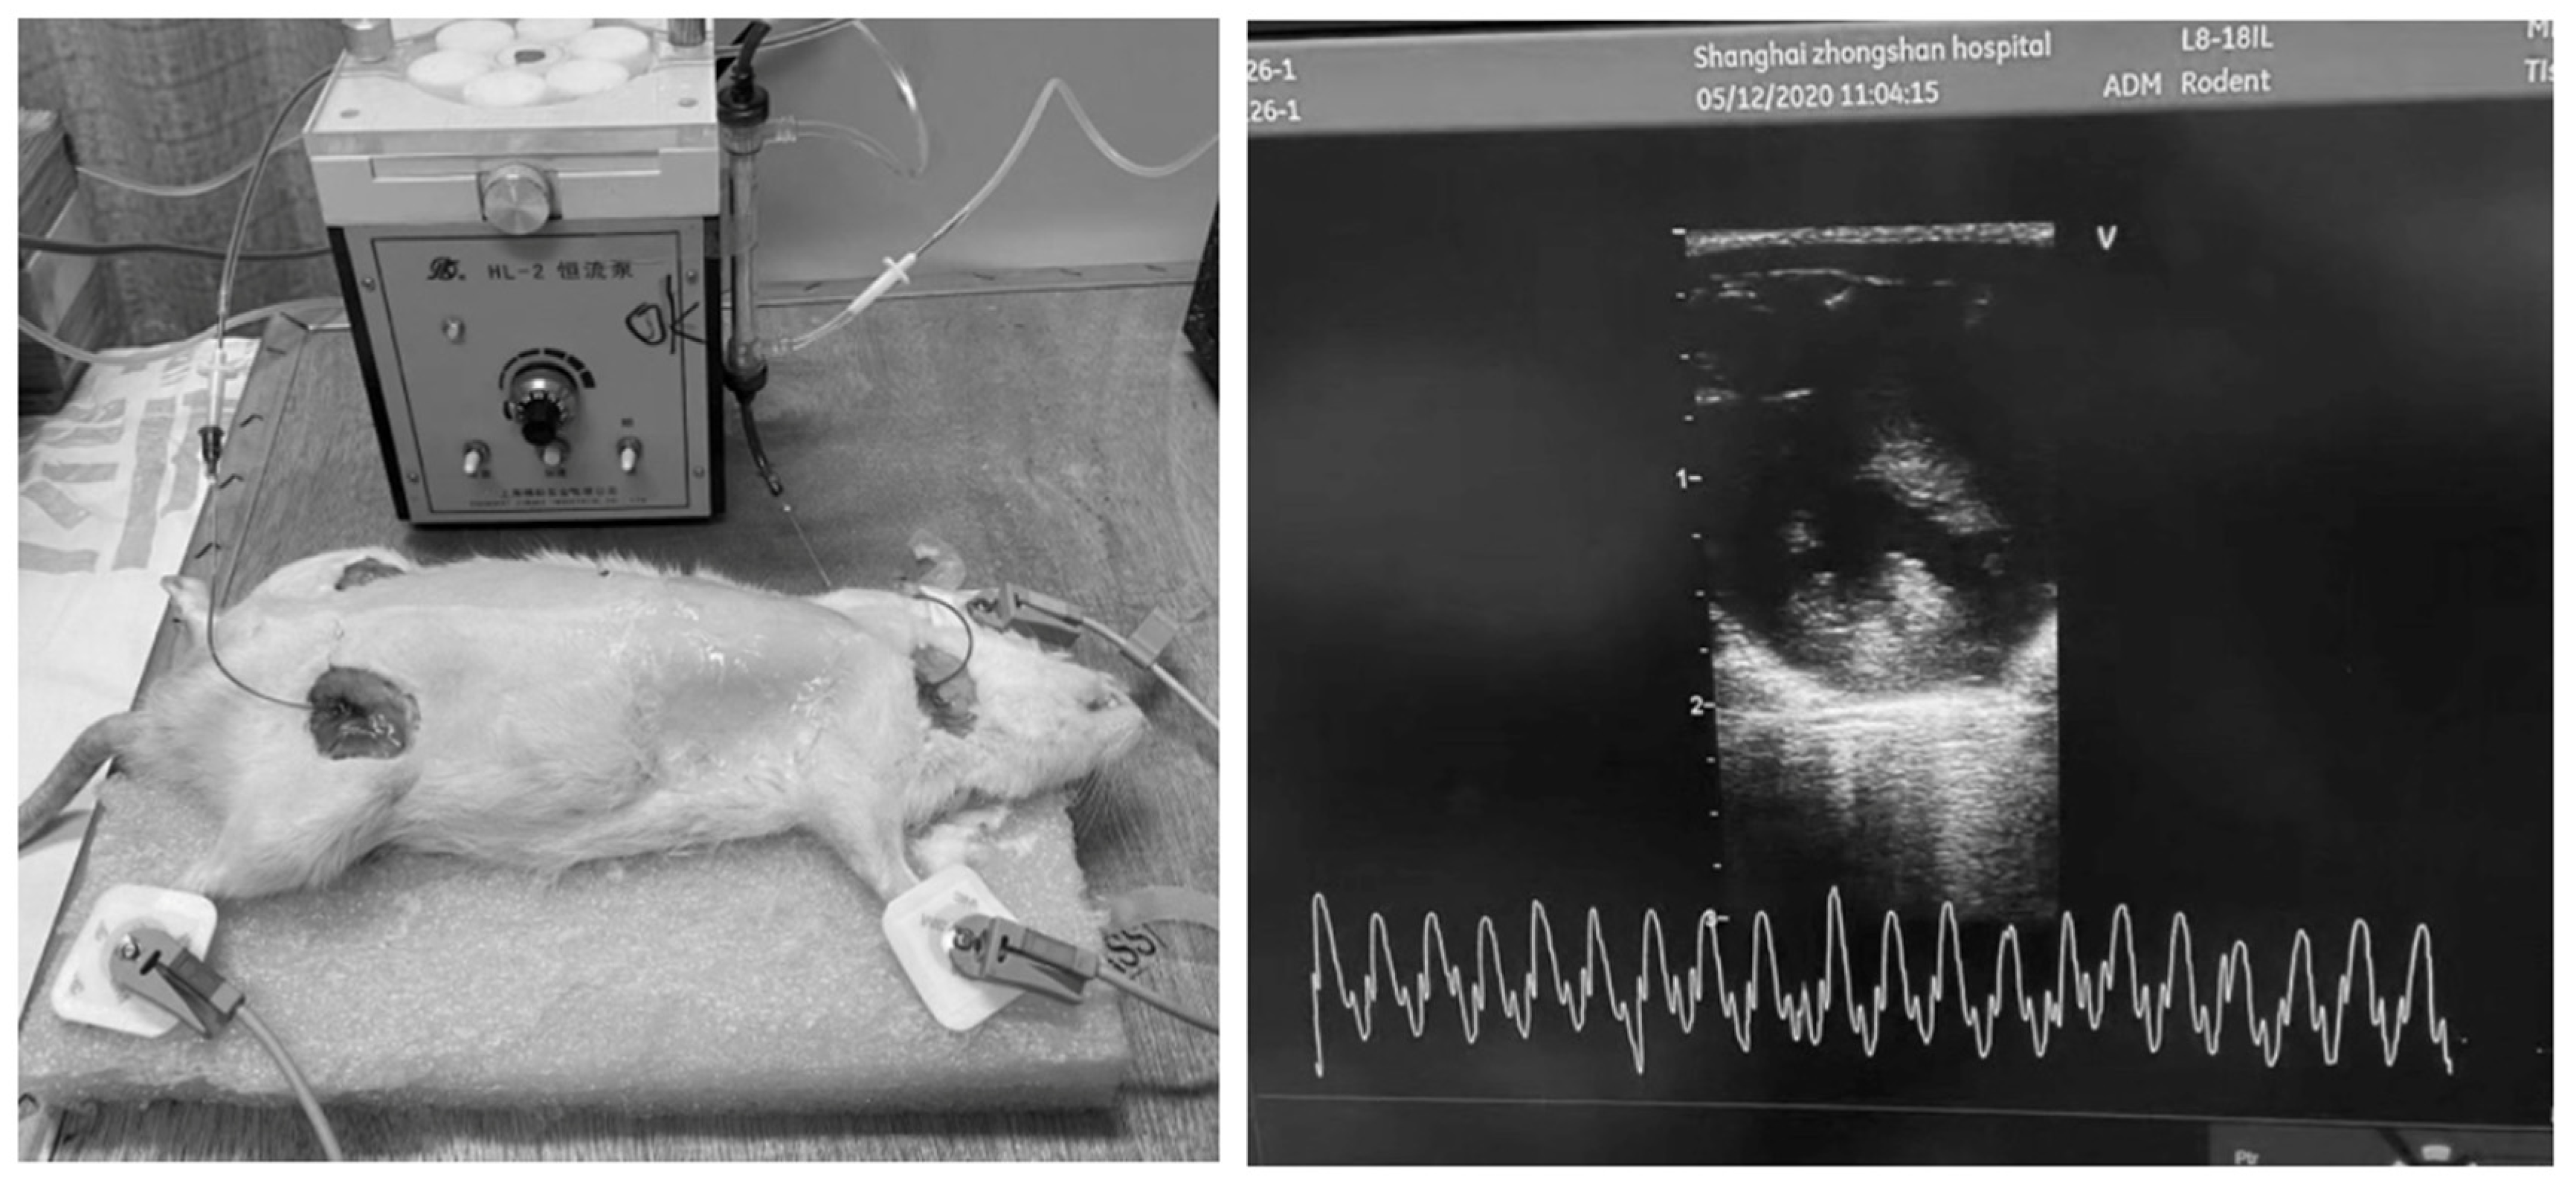

Hemodialysis was conducted over a duration of 2 h, with continuous monitoring under anesthesia and systemic anticoagulation using heparin. Following the treatment, extracorporeal circulation was terminated, and the blood within the circuit was safely reinfused into the rats using an air-driven method (Figure 1).

Figure 1. Hemodialysis and echocardiographic monitoring in rats.